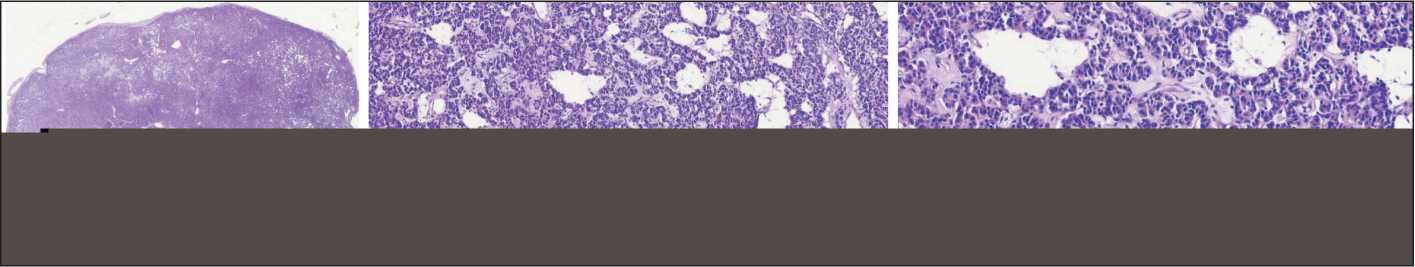

При микроскопическом исследовании: опухоль преимущественно тубулярного типа строения, с отчетливыми гландулярными структурами с периваскулярным типом роста и образованием розетковидных формирований (рис. 2). Клетки мономорфного типа с округлым ядром с гранулярным нежным хроматином по типу «соль и перец», единичными мелкими ядрышками. Митотическая активность низкая (менее 2 митозов на 2 мм2). Строма по периферии в виде тонких гиалинизиро-ванных прослоек. При ИГХ-исследовании выявлена выраженная экспрессия опухолевыми клетками Chromogranin A. Также выявлена экспрессия Synaptophysin, CD56, TTF1 (рис. 3). Индекс проли-

Рис. 2. Микрофото. Образование отграничено от окружающей ткани без инфильтративного роста (а), преимущественно с тубулярным типом строения с построением отчетливых гландулярных структур с периваскулярным типом роста и образованием розетковидных формирований с клетками с округлым ядром и гранулярным нежным хроматином по типу «соль и перец», единичными мелкими ядрышками. Митотическая активность низкая (менее 2 митозов на 2 мм2 (б–в)). Окраска гематоксилином и эозином; а – ×4; б – ×10; в – ×20. Примечание: рисунок выполнен авторами

Fig. 2. Microphoto. The lesion is delineated from the surrounding tissue without infiltrative growth (a), predominantly with a tubular type of structure with the formation of distinct glandular structures with a perivascular type of growth and rosettes with cells having a rounded nucleus with granular, delicate chromatin in a “salt and pepper” pattern, and single small nucleoli. Mitotic activity is low (less than 2 mitoses per 2 mm2 (b–c). Hematoxylin and eosin staining; a – ×4; b – ×10; c – ×20. Note: created by the authors